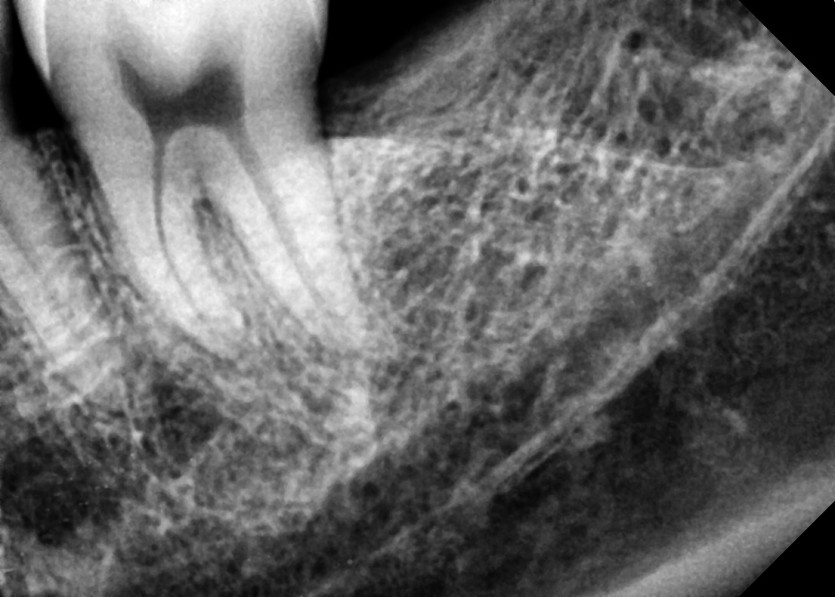

#28,38 사랑니 발치

구강 외과 전문의가 당일 발치했습니다.